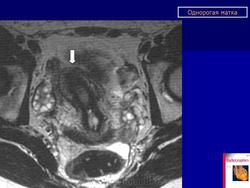

МПС. Женская репродуктивная система. Аномалии и варианты развития. Матка. Однорогая матка. +

Аномалии и варианты развития. Однорогая матка.